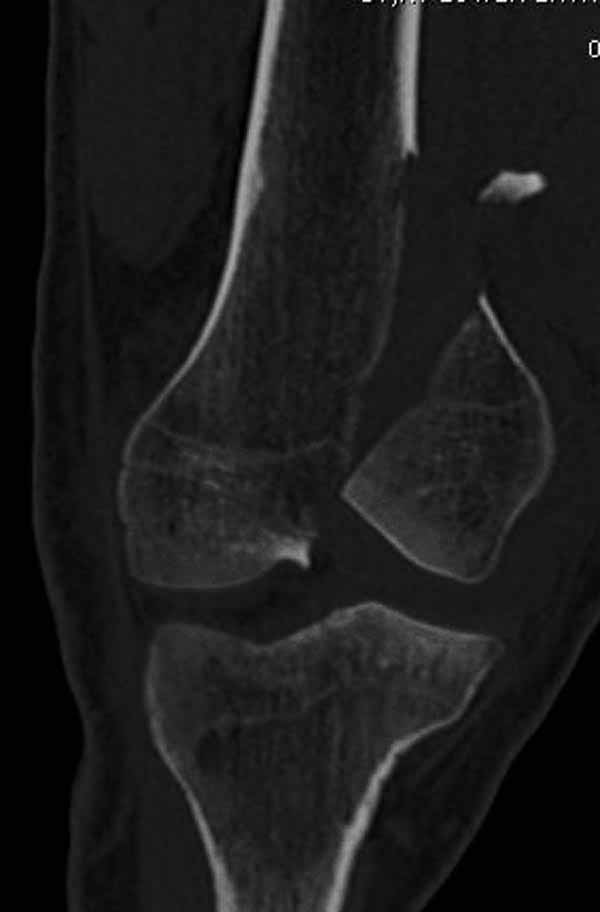

А теперь по поводу лечения перелома. Среди всех чрез/меж-мыщелковых переломов в 38% сопровождются переломом в корональной плоскости, т.е перелом Hoffa. Nork et al, J Orthop Trauma, 87:564, 2005.

У больных как в этом случае, с вовлечением двух мыщелков правильно, что сделали вытяжение до операции. Здесь имеется флексионный компонент на другой стороне, и я бы рекомендовал операцию делать из двух доступов. Сперва фиксировать медиальную колонну custom made пластиной, обычно 1/3 тубулярной пластиной в 4.5 мм, потому что пока производители опаздывают с медиальной пластиной.

Пластину надо устанавливать на апексе перелома, иначе фрагмент начнет сползать. А на второй стороне, если имеется большой одиночный фрагмент тогда проблем не бывает, и их можно собрать компрессирующими винтами. Проблема наступает тогда когда многофрагментраность на латеральной стороне, где надо применить комбинированный метод, иногда несколькими пластинами. Или сменой позиции установки пластины, чтобы максимально прикрыть перелом и создать боковую поддержку.